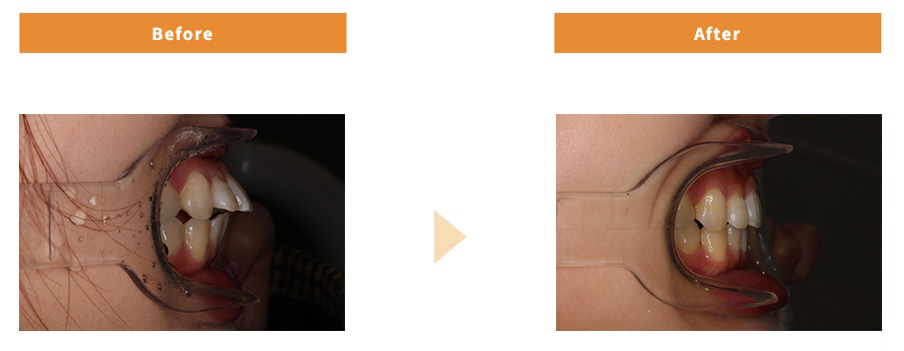

ワイヤー矯正

| 治療費用 | 836,000円 |

|---|---|

| 治療期間 | 3年間 |

| 患者様の主訴 | 出っ歯が気になる |

| 治療内容 | 表側ワイヤー矯正 |